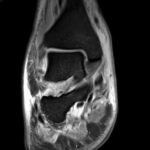

Septic arthritis of native joints is uncommon, but the condition can be threatening to life and limb if left untreated.1 Septic arthritis of the acromioclavicular (AC) joint of the shoulder is particularly rare and has only appeared sparsely in medical literature, mainly through individual case reports. Early recognition and treatment of the condition is vital, but diagnosis of septic AC arthritis can be difficult due to its presentation with vague symptoms and nonspecific laboratory findings. This case report describes the care of a patient with poorly managed diabetes who presented to the emergency department with one month of pain and swelling of the left shoulder and two weeks of pain and swelling in the right ankle. Imaging revealed fluid in the AC joint, and laboratory evaluation showed an elevation in inflammatory markers, including leukocyte count, C-reactive protein (CRP), and erythrocyte sedimentation rate (ESR). The patient’s hospital course was complicated by methicillin-sensitive Staphylococcus Aureus bacteremia without evidence of sepsis. The patient underwent open debridement and washout of both the ankle and AC joint without complication. After recovery, the patient was discharged to a rehabilitative center with IV antibiotics and weekly follow up care with infectious disease specialists. This case illustrates the importance of early diagnosis and treatment of septic arthritis, even in less common joint spaces, to prevent progression of this dangerous disease.